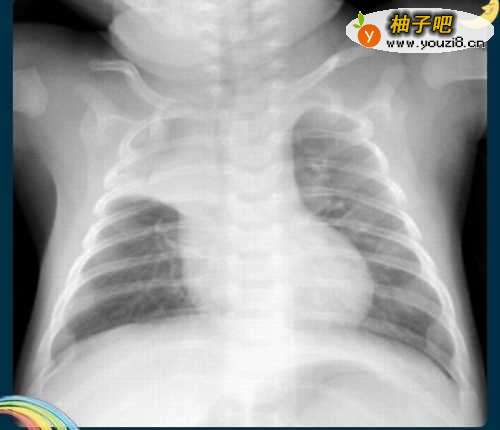

4彩超结果出来了,医生一看,大吃一惊。说你如何搞的,病成这样,才到医院里来,以前你在干啥。自己的身体不当回事。肺部的阴影已经快要布满整个肺部了。

5医生告诉家人,已经是肺癌了。可以不可以治好,不好说,尽人事听天命吧。现在那个后悔呀,早知如此,何必当初。